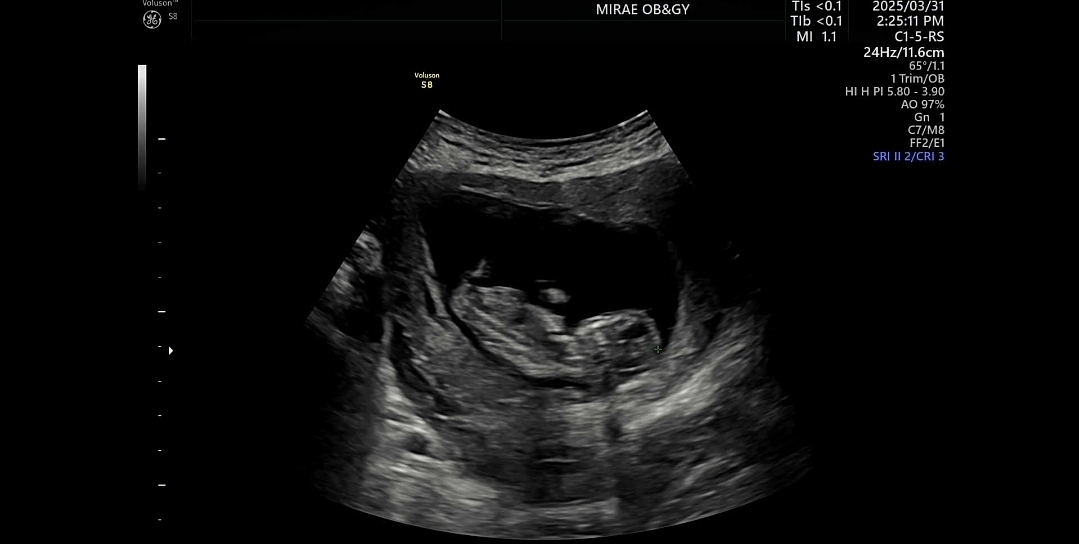

저도 성별이 궁금해요

각도법으로 성별아시는 고수님들 부탁드릴께요 ㅠ ㅠ